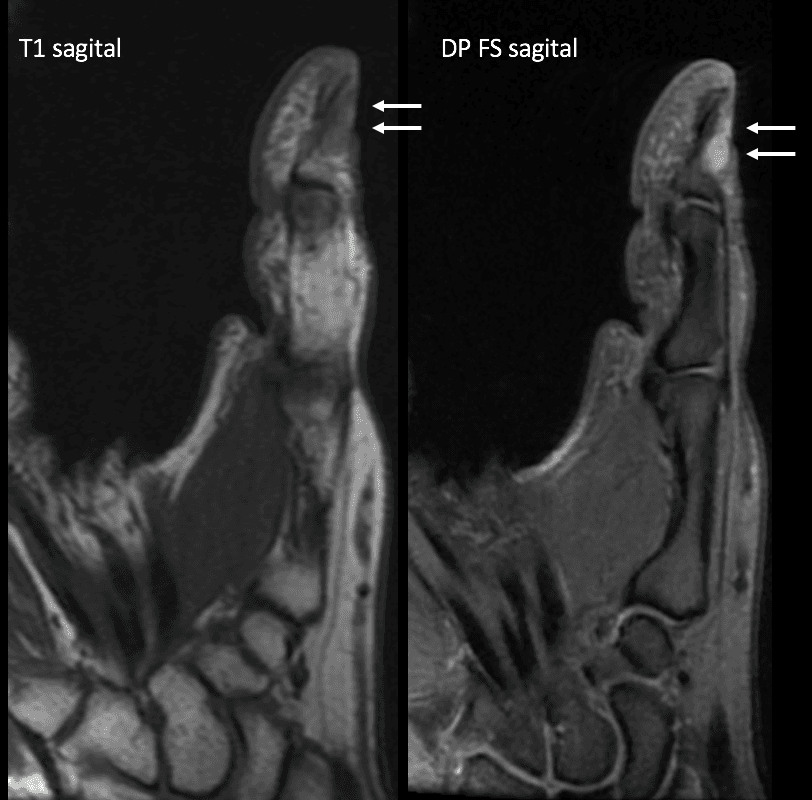

RM do primeiro quirodáctilo em plano sagital, sequências ponderadas em T1 e em densidade protônica com saturação de gordura.

Observa-se imagem nodular sólida com sinal intermediário em T1 e alto sinal em densidade protônica com saturação de gordura, localizada junto ao leito ungueal da falange proximal do I dedo com contornos regulares e limites bem definidos.